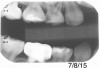

Figure 13 shows a bitewing of a 7-year-old girl with Williams syndrome who had previously required treatment under general anesthesia (GA) in a hospital setting for treatment of caries in her primary teeth. An incipient lesion on the mesial of her lower right permanent first molar, tooth No. 30, was treated more conservatively, in office, with resin infiltration, which allowed her to avoid more invasive treatment and the possible need for another GA. The lesion was arrested (Figure 14) and has been stable for over 5 years.

Fig 13. Bitewing of a 7-year-old girl. F

Figure 13

Fig 14. Same patient more than 3 years later.

Figure 14